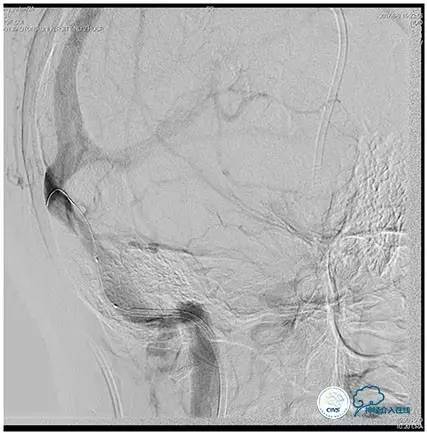

术中造影

5ml/s,总量8ml,压力100~150